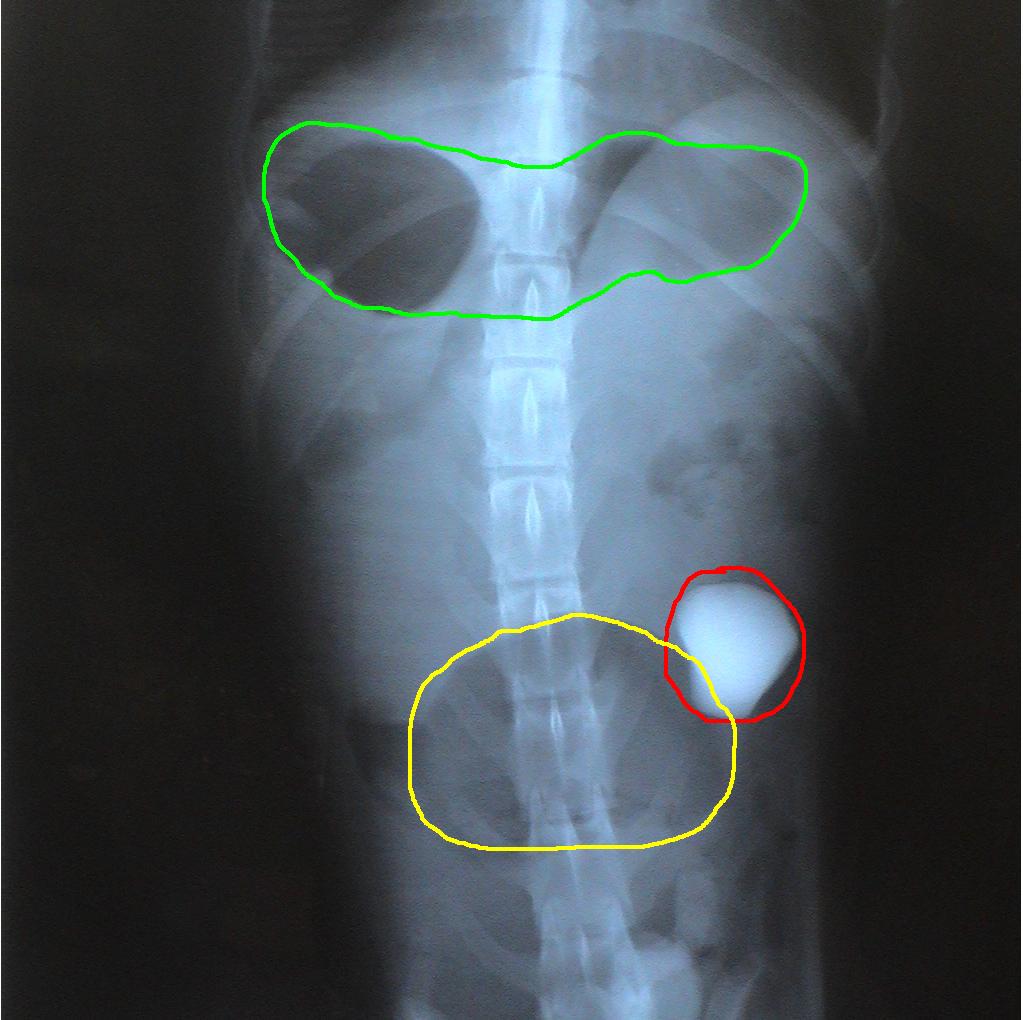

Two sets of radiographs are always taken to localize lesions and identify problems. Radiographs are flat pictures of three-dimensional animals! If one view is taken, things can be lost as structures will overlap each other. For example, the rock is located on the left side of the abdomen which is clearly evident on the second set of radiographs. This is not evident in the first set since the left and right sides of the dog overlap each other.

Notice the difference in the shape of the circled structures depending on the position of the animal.